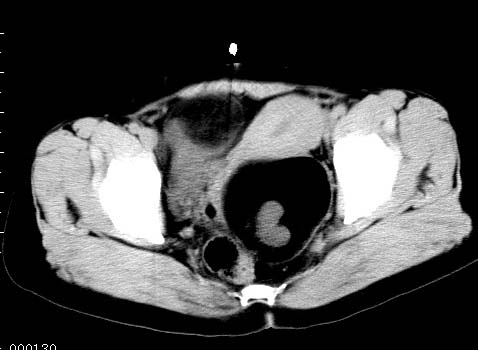

女性 病人 44岁 盆腔 下腹部痛1天!

盆腔多发畸胎瘤

盆腔内低密度为主混杂等密度及少许囊样与班状钙化影,如果做了肠道准备就好了。支持畸胎瘤。当然做mri会更好

典型的双侧附件畸胎瘤.